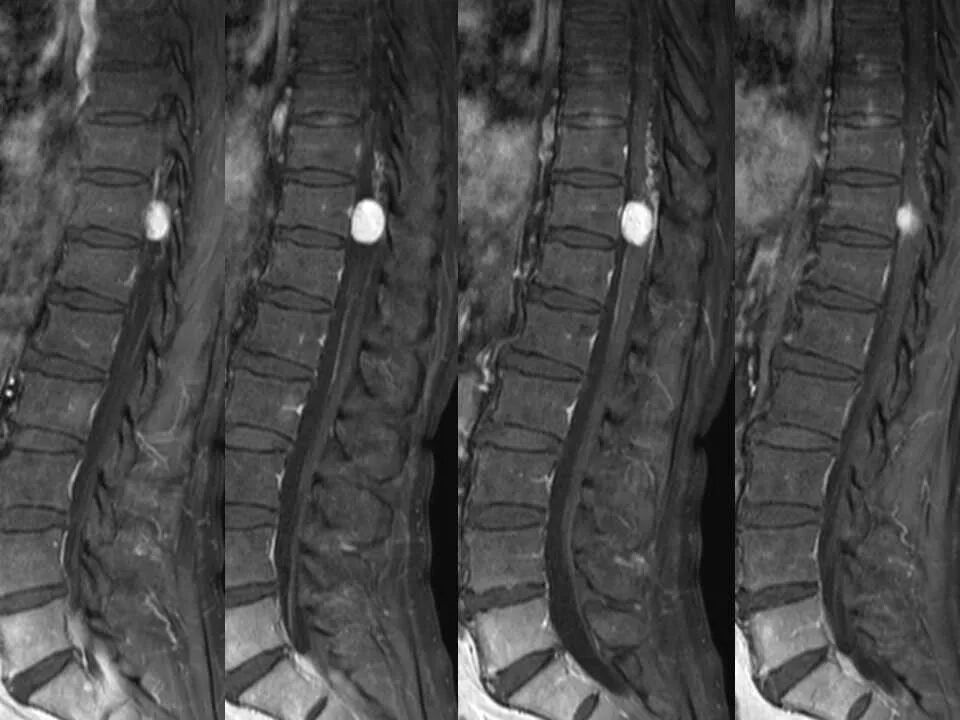

北方影像联盟 一周病例精选之“椎管占位”